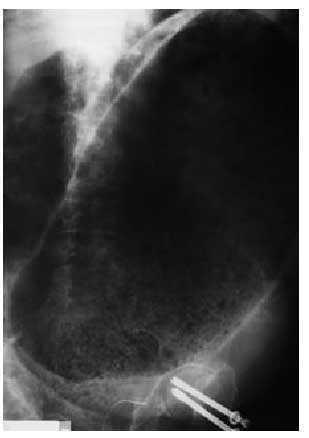

Fig. 2. Radiografía de abdomen. Importante disminución de la dilatación del rectosigma.

Unas horas después se realizó una nueva radiografía de abdomen en la que se observaba una importante disminución de la dilatación del rectosigma (fig. 2). En función de estos datos fue diagnosticado de síndrome de Ogilvie.